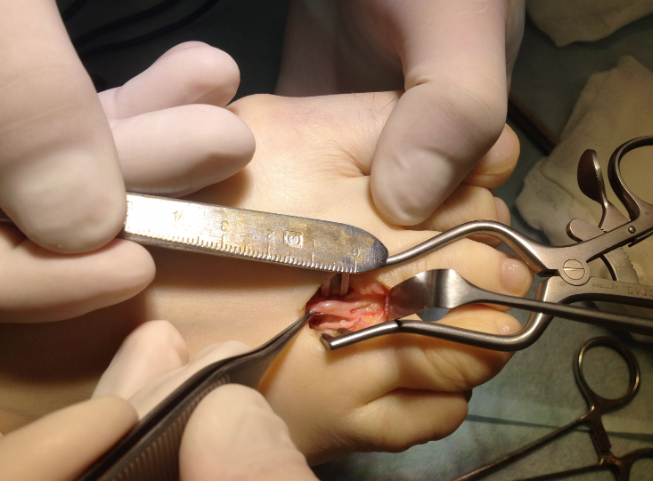

Если болезнь находится в запущенном состоянии, ее прогресс останавливают только операцией. Хирурги предлагают вскрыть плюсневый канал, рассечь или удалить неврому. Все операции проводятся под общим наркозом.

Хирургические методы:

Редкие случаи запущенной болезни требуют искусственно переломить кость, чтобы сместить ее и освободить сдавленные нервные ткани. Такая операция проводится без разрезов, с рентген-контролем.